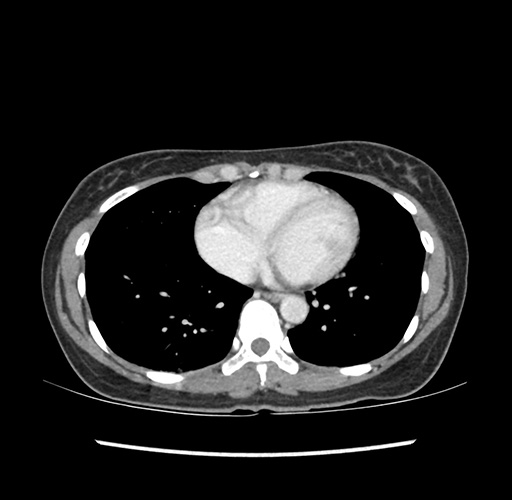

Imaging Analysis

Look through the patient's CT scan to identify any areas of concern for the necessary procedure.

Based on your CT findings, which issue(s) would give reason for "planned slowing down moment(s)" in this case?

Considering a standard left lateral sectionectomy procedure, what step(s) of the operation would you do differently in this case ?